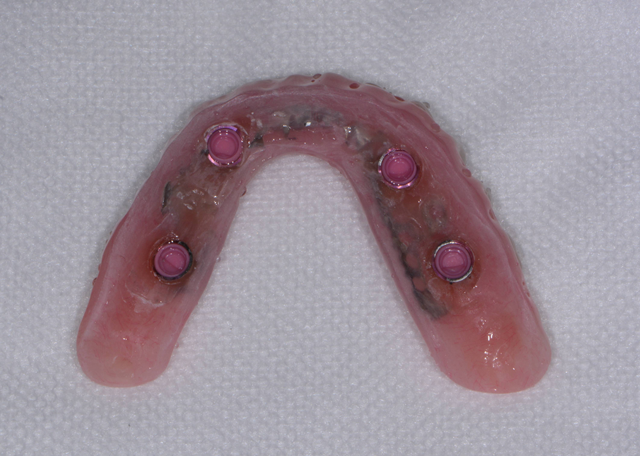

A previously made, metal-reinforced overdenture with relieved areas for the housings was tried in to confirm comfort and fit. Any interference that was detected between the denture base and attachments and housings was checked and eliminated.

When relining dentures or picking up overdenture attachments directly within the mouth, the patient may experience heat generation that is uncomfortable in addition to a bad taste when using methyl methacrylate-based pickup materials. Since Rebase II, a chairside hard denture reline material (Tokuyama Dental), is methyl methacrylate free, it doesn’t have a strong odor or taste, and it has minimal heat generation, making it a much better experience for the patient. Rebase II’s mechanical strength also makes it a suitable option for pickup applications.

Fig. 15 Fig. 16

The first step was to brush a thin coat of adhesive into the overdenture recesses (Fig. 14) to enhance retention between the denture base and the hard reline material. Petroleum jelly was applied to the surrounding surfaces of the denture to prevent unwanted adherence of excess material. Once mixed, the Rebase II material (Figs. 15 & 16) was placed into a plastic dispensing syringe and injected up to two-thirds the height of each recess as well as on to the attachments. During seating, the prosthesis was gently held in place by hand. After a total of about three minutes, the overdenture with the incorporated retention caps was removed. Any excess material was removed with a trimming bur (Fig. 17). At the completion of the prosthetic phase, the patient stated how pleased she was to be able to smile and function without the prosthesis wobbling or falling out (Fig. 18). Most importantly from a clinical standpoint, we were pleased to see the areas in the upper and lower arches healthy and infection-free.